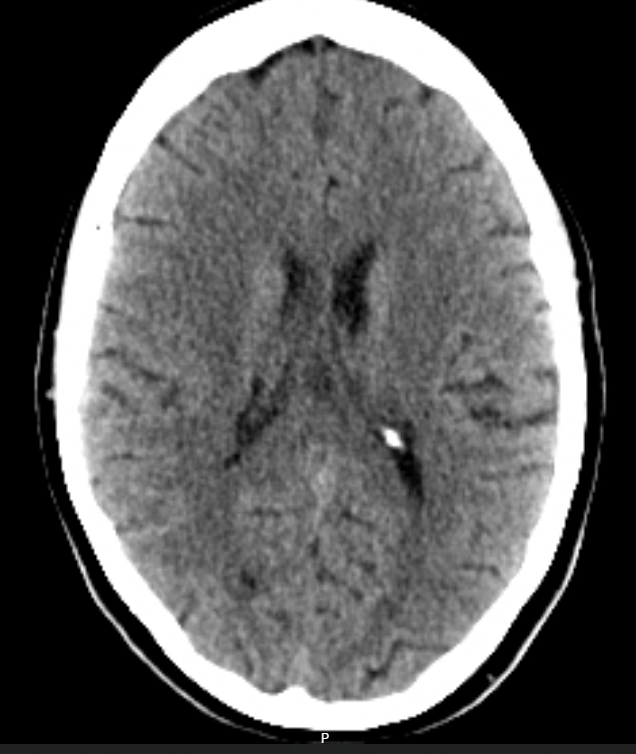

A CT-Brain is urgently booked 2 days later. (Click to open images)

Describe these CT images

Axial slices

Large hypodense space-occupying lesion in the right frontal/pareital lobe

Poorly defined borders

Midline sulcal effacement and minor midline shift

No ventricular obstruction

No obvious signs of raised ICP